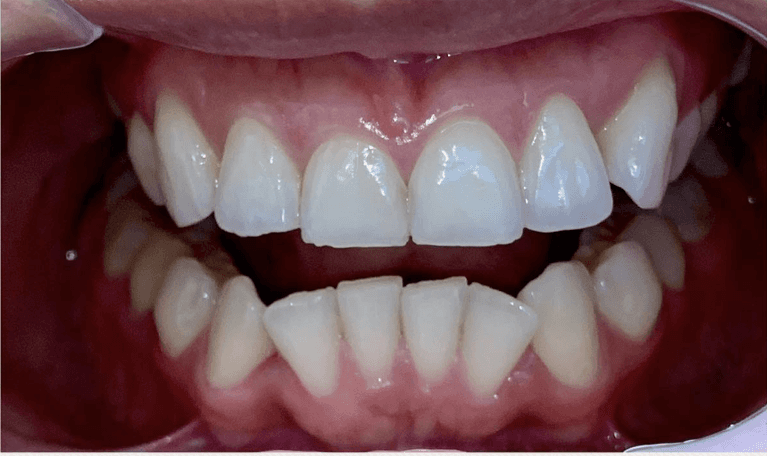

Before and after with Invisalign orthodontic treatment. Pictures taken with different phones at different setting. Used total of 27 aligners/trays. Treatment time 13.5 months